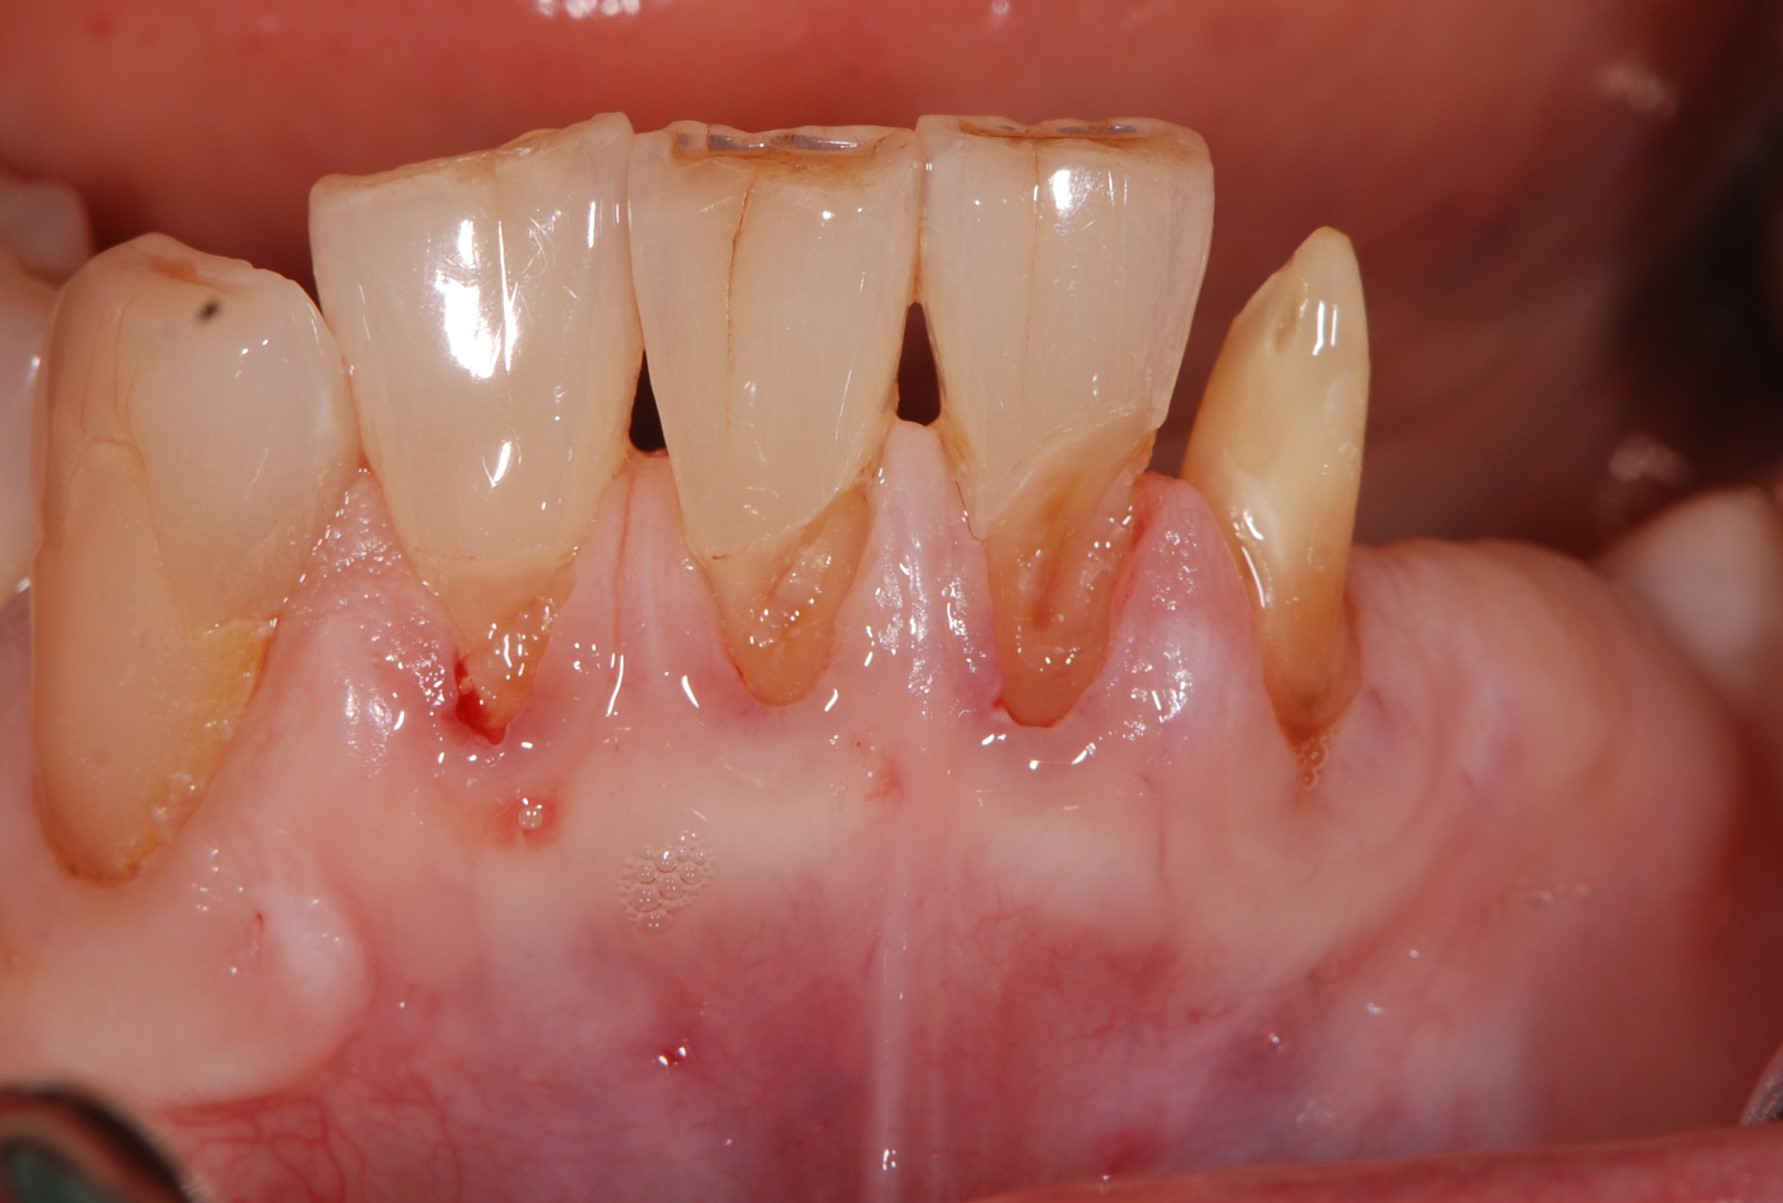

• 治療前

古い詰め物と虫歯を取った状態。血管が透けて見えるほど薄い歯茎である。このような歯茎は歯ブラシが当たると痛みを感じやすい。